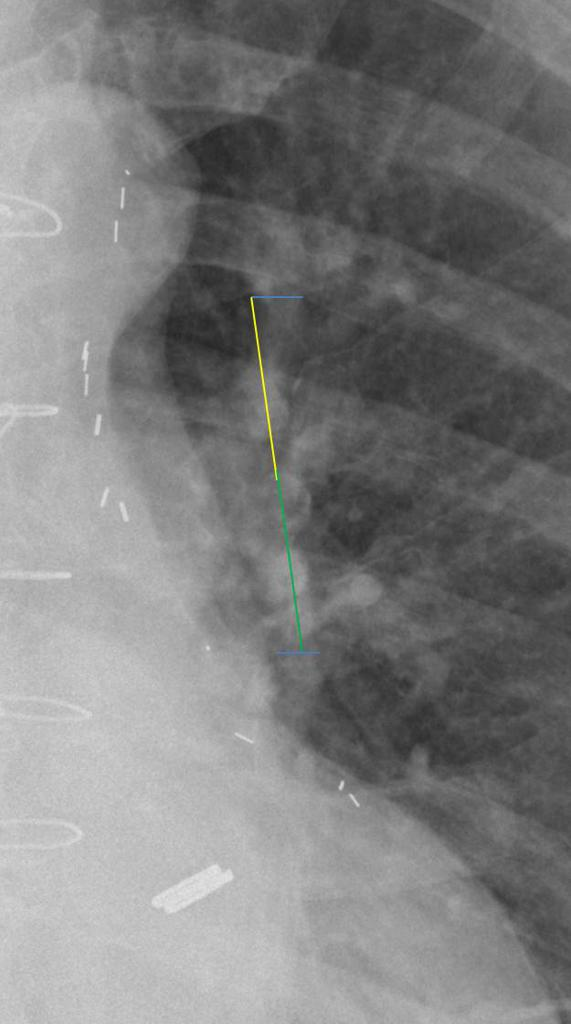

Hiler nokta/açı, superior pulmoner ven (sarı çizgi) ve inen pulmoner arter (yeşil çizgi) dikkate alınır.

1- Genişlemiş üst lob damarları (sefalizasyon); Sefalizasyon, kanın üst lob damarlarına yeniden dağıtılması anlamına gelir. Hidrostatik basınç 10 mm Hg’yi aştığında, sıvının akciğerin interstisyumuna sızmaya başladığı varsayılmıştır. Bu fazla sıvı başlangıçta muhtemelen yerçekiminin bir sonucu olarak alt lob damarlarını sıkıştırır. Bundan sonra, daha büyük hacimde kan dağıtmak için üst lob damarları görevlendirilir. Daha fazla kan taşımak için üst lob damarlarının boyutu artar.